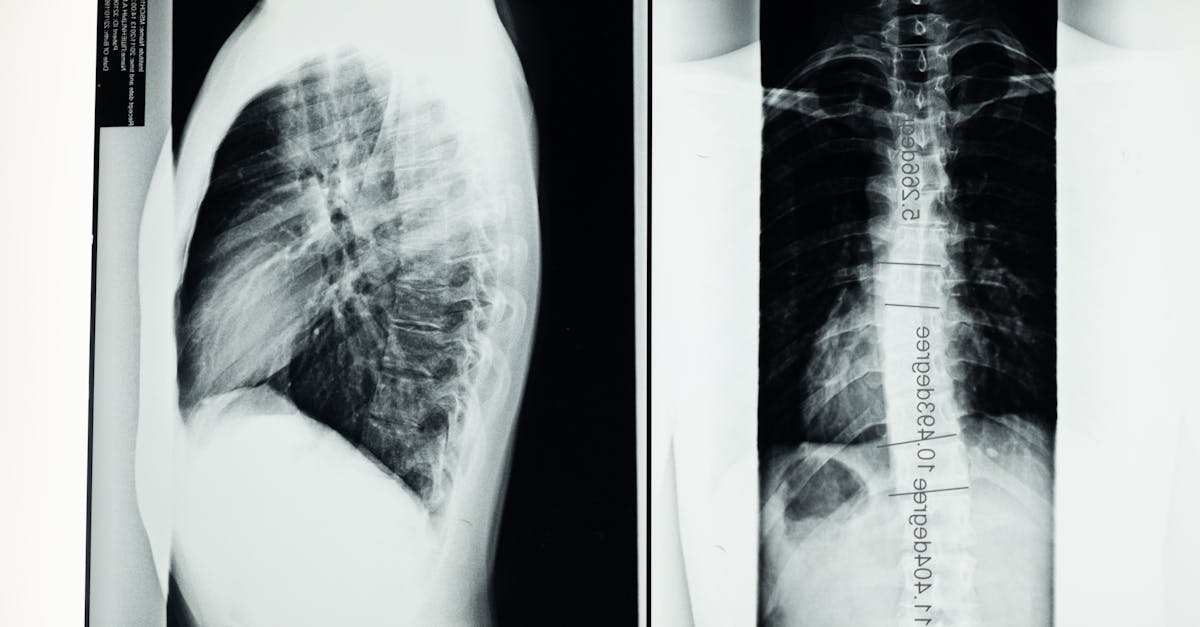

Understanding Scoliosis

Scoliosis is a medical condition characterized by an abnormal lateral curvature of the spine. Instead of maintaining a straight alignment, the spine curves to the side, resembling an “S” or “C” shape. This condition can affect individuals of all ages, but it is often diagnosed during adolescence. Scoliosis can range from mild to severe, and in some cases, it may require medical intervention.

Types of Scoliosis

There are several types of scoliosis, each with unique causes and characteristics. Understanding the different types can help in identifying the appropriate treatment and management strategies.

Idiopathic Scoliosis: The most common type, with no known cause. Typically diagnosed in adolescents.

Congenital Scoliosis: Caused by abnormal spinal development before birth.

Neuromuscular Scoliosis: Associated with neurological or muscular conditions like cerebral palsy or muscular dystrophy.

Degenerative Scoliosis: Occurs in adults due to spinal degeneration or arthritis.